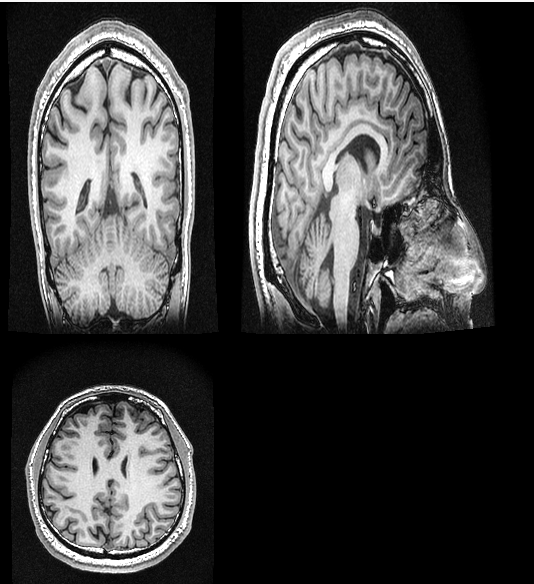

However, the image seems stretched in the z-direction, which is also the slice direction (i.e. the 3DT1 was acquired in axial mode).

Please find a screenshot attached to this message.